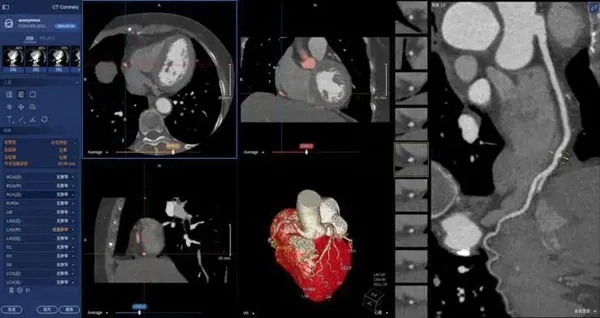

在医学领域,机器视觉主要用于医学辅助诊断。首先采集核磁共振、超声波、激光、X射线、γ射线等对人体检查记录的图像,再利用数字图像处理技术、信息融合技术对这些医学图像进行分析、描述和识别,最后得出相关信息,对辅助医生诊断人体病源大小、形状和异常,并进行有效治疗发挥了重要的作用。不同医学影像设备得到的是不同特性的生物组织图像,如X射线反映的是骨骼组织,核磁共振影像反映的是有机组织图像,而医生往往需要考虑骨骼有机组织的关系,因而需要利用数字图像处理技术将两种图像适当地叠加起来,以便于医学分析。